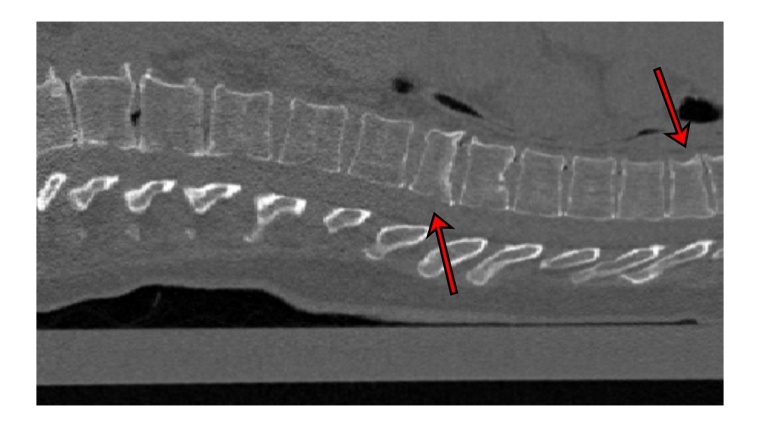

Oft werden CT-Bilder vom Brustkorb aufgenommen, um zum Beispiel die Lunge anzuschauen. Die Wirbelsäule ist zwar auf dem Bild zu sehen, wird aber nicht geprüft, weil ein anderes Problem im Vordergrund steht. „Unser Programm kann bei solchen Untersuchungen im Hintergrund laufen. Es schaut sich automatisch die Wirbelsäule an und gibt einen Hinweis auf Frakturen der Wirbelkörper, die ansonsten vielleicht nicht entdeckt worden wären“, erklärt Erstautor Yilmaz. Das ist wichtig, denn das Vorhandensein von Wirbelfrakturen erhöht das Risiko weiterer Brüche erheblich. Die Software arbeitet mit neuronalen Netzen. An 159 CT-Bildern der Wirbelsäule, die aus sieben Krankenhäusern Deutschlands stammten, wurde die KI getestet. Erfahrene Radiologen begutachteten zuvor die Bilder und entdeckten 170 Frakturen. „90 Prozent der Fälle mit Frakturen klassifizierte das neuronale Netz korrekt sowie 87 Prozent der Wirbel ohne Frakturen“, berichtet Yilmaz.

Schweregrad des Bruchs differenzieren